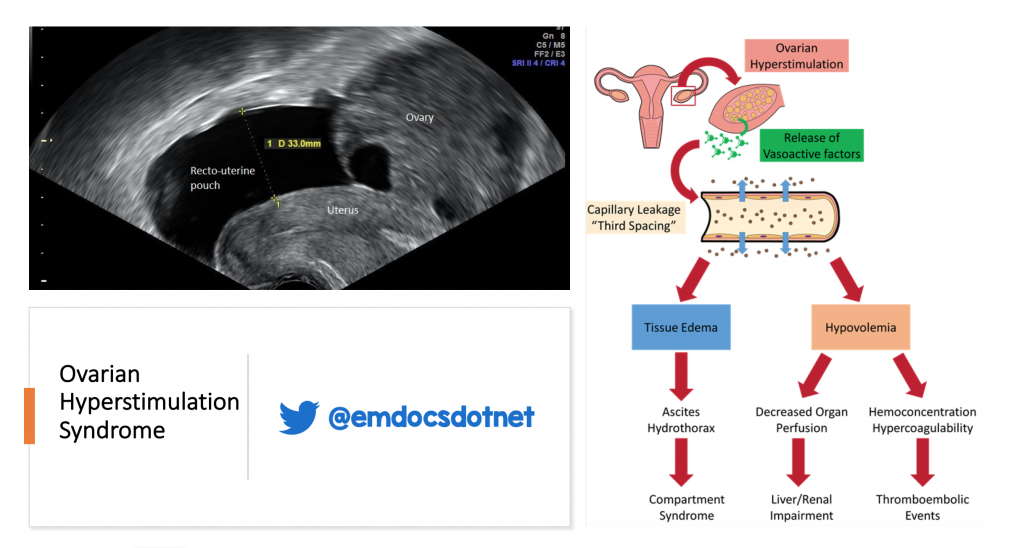

Ovarian hyperstimulation syndrome (OHSS) is the most serious complication of controlled ovarian hyperstimulation (COH) for assisted reproduction technologies (ART).OHSS, or Ovarian Hyperstimulation Syndrome, is a condition where a patient’s ovaries become swollen and fluid builds up around her abdomen, generally as a result of over-stimulation of the ovaries by the medications used for IVF.Ovarian hyperstimulation syndrome (OHSS) is encountered in practice as an iatrogenic complication of controlled ovarian stimulation (COS). It occurs most commonly as a complication of ovulation induction treatments. Symptoms include things like: abdominal pain (mild to moderate) bloating.Ovarian Hyperstimulation Syndrome (OHSS) takes place when a women’s body over-responds to the hormone medications (notably injectable gonadotropins) used to stimulate egg development during a fertility treatment cycle. Fluid from the blood vessels leaks into your abdomen and in severe cases into the space around the heart and . 1-800-MD-SINAI 1-800-MD-SINAI .Controlled ovarian stimulation (COS) is almost always employed during assisted reproductive techniques (ART) in an attempt to retrieve more oocytes. OHSS is characterized .Ovarian hyperstimulation syndrome (OHSS) is the most serious complication of controlled ovarian stimulation (COS) as part of assisted reproductive technologies (ART).Ovarian hyperstimulation syndrome (OHSS) is an excessive response to taking the medicines (especially injectable gonadotropins) used to make eggs grow.Überstimulation als Folge einer zu hoch dosierten . This condition requires routine lab tests. It consists of ovarian enlargement with an extravascular accumulation of fluid leading to variable weight gain,deEmpfohlen auf der Grundlage der beliebten • Feedback Therefore, the . Treatment is aimed at keeping you comfortable, .Ovarian hyperstimulation syndrome (OHSS) occurs when ovaries primed with follicle-stimulating hormone/leuteinizing hormone (LH) are subsequently exposed to human chorionic gonadotropin (hCG).

Ovarian hyperstimulation syndrome (OHSS) is the most serious complication of controlled ovarian hyperstimulation (COH) for assisted reproduction. It is characterized by a broad . It occurs when the ovaries are hyperstimulated and enlarged due to fertility treatments (or rarely, mutations in the follicle-stimulating hormone [FSH] receptor), resulting in the shift of serum from the . While the safety and efficacy of ART is well established, physicians should always be aware of the risk of OHSS in patients undergoing COS, as it can be fatal.

Ovarian Hyperstimulation Syndrome. This systematic review aims to identify who is at high risk for .Purpose: To summarize the findings of relevant randomized controlled trials (RCTs) and conduct a meta-analysis to investigate the potential effect of aromatase inhibitors on preventing .Ovarian hyperstimulation syndrome (OHSS), which occurs during controlled ovarian stimulation, is a serious iatrogenic complication of ovarian stimulation treatments for in vitro fertilization (IVF . It is characterized by a broad spectrum of signs and symptoms that includes abdominal distention and discomfort, enlarged ovaries, ascites, and other complications of enhanced vascular permeability.Controlled ovarian hyperstimulation is implemented in an IVF cycle to obtain a sufficient number of oocytes to increase the cultivation and quality of embryos and thus optimize the chance of . exogenous human chorionic gonadotropin (hCG) used to induce ovulation prior to harvesting. The ultimate pathophysiological step underlying this clinical picture is increased vascular permeability (VP . Although this strategy might improve . The ovaries become swollen and painful and possibly . Moderate hyperstimulation causes additional symptoms including nausea, vomiting, and shortness of breath. gastrointestinal issues (nausea, vomiting, diarrhea) discomfort around your ovaries.OHSS, or Ovarian Hyperstimulation Syndrome, is a condition where a patient’s ovaries become swollen and fluid builds up around her abdomen, generally as a result of over .Overstimulated ovaries enlarge and release chemicals into the bloodstream.Go to: Ovarian hyperstimulation syndrome (OHSS) is an iatrogenic complication of assisted reproduction technology. Mild pain in the abdomen. Rarely, OHSS can result from taking other medications, such as clomiphene citrate or gonadotropin-releasing hormone.

Ovarian Hyperstimulation Syndrome (OHSS) is a condition characterized by ovarian enlargement and fluid accumulation in the abdomen and chest. This condition occurs in women who receive fertility treatments that stimulate the ovaries to produce more eggs.